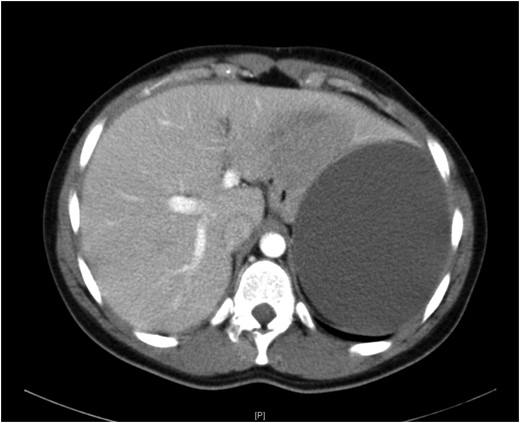

A 19-year-old female presented with a 2-day history of severe left upper abdominal pain. There was no known history of abdominal trauma or travel outside the UK. She was systemically well, had a soft abdomen with exquisite tenderness at the left upper quadrant and loin regions. The provisional blood tests, hydatid serology and chest and abdominal X-rays were unremarkable. An ultrasound scan showed a large splenic cyst with no increase in vascularity on Doppler assessment, while an intravenous contrast-enhanced CT scan showed a 12.5 × 9.7 × 10.7 cm well-defined cystic mass arising from the upper pole of the spleen (Fig. 1) with multiple fine echogenic shadows and medial displacement of the stomach and the left kidney (Fig. 2). Findings were consistent with the diagnosis of a simple splenic cyst. The patient was scheduled for an urgent laparoscopic de-capsulation, and received triple vaccination (meningococcal, pneumococcal and Haemophilus influenzae type B). Although 2 weeks are recommended between vaccination and splenectomy should this be needed, we proceeded to surgery after 10 days from vaccination as the patient was considerably troubled with abdominal pain and we were confident that a total splenectomy could be avoided.

Computed tomography showing medial displacement of the stomach and the left kidney by the cyst.